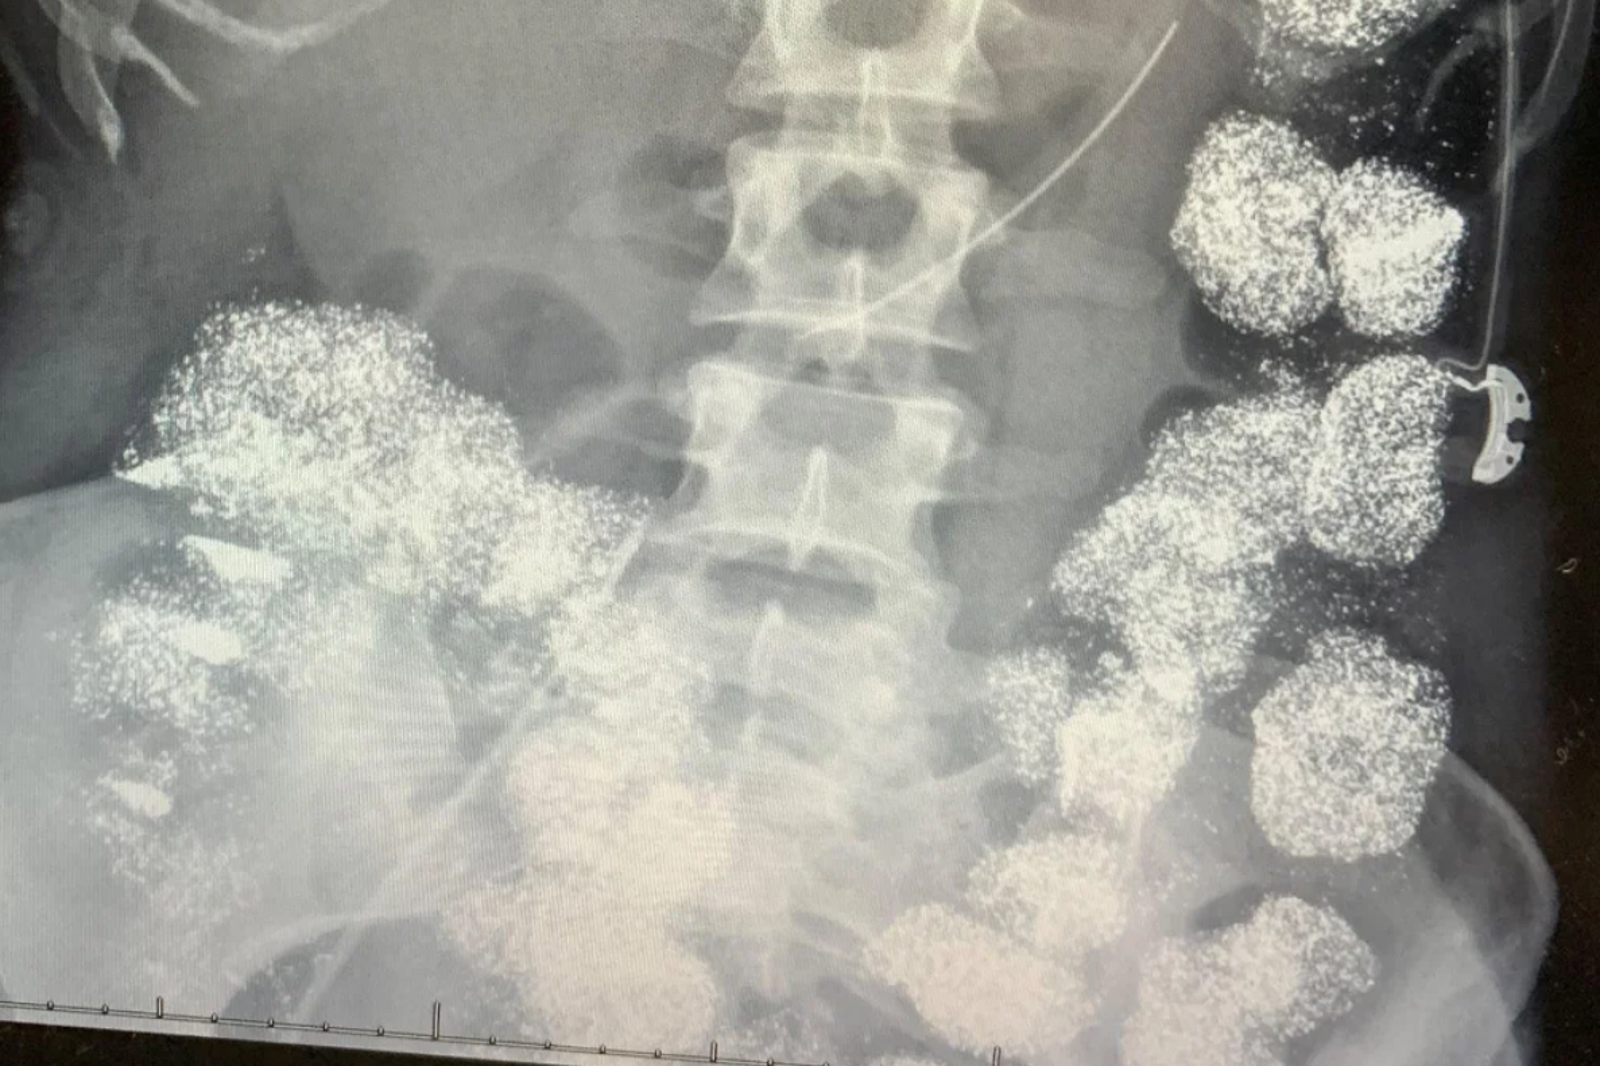

「她的腸子裡全是鉛,骨頭裡也有鉛,幾乎百分之百都是鉛,到處都是」美國阿拉巴馬州一名女子漢娜.佩蒂(Hannah Pettey)母親描述,她的女兒差點被慢性鉛中毒奪命,原以為只是身體不適、體力下滑,竟是漢娜丈夫布萊恩.曼恩(Brian Mann)數月的謀殺計畫;檢方指控其為了奪取鉅額保險金,在漢娜每日服用的保健膠囊中摻入「鉛」,導致身體逐漸衰弱、瀕臨死亡,最終法院裁定布萊恩罪名成立,判處無期徒刑。

醫療團隊指出,漢娜不僅體內血液含鉛,骨骼、消化道都被鉛侵蝕,經重症病房進行螯合治療(Chelation Therapy),醫師坦言,漢娜能夠活下來,堪稱奇蹟;而警方展開調查後,發現最可疑的人正是她的丈夫布萊恩,其為一名脊骨治療師,調查發現,布萊恩長期以照顧妻子健康為由,親手為她準備「每日營養膠囊」,卻在他診所與住宅內搜出鉛片、空膠囊及混合器具,化驗結果顯示,這些化學成分與漢娜體內檢出的來源相符。